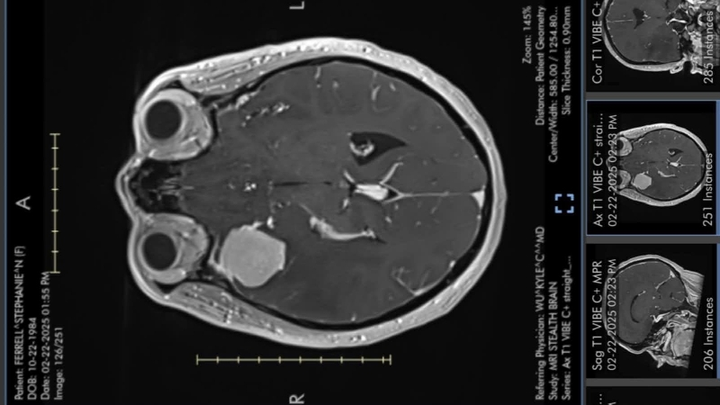

In November 2024, my mother began experiencing auras, the subtle signals your body provides before the onset of a seizure. By early February 2025, she suffered her first actual seizure. Although she was prescribed medication, she continued to struggle with debilitating headaches and excruciating eye pain. On February 21, in desperation due to the persistent pain, she visited the emergency room. After undergoing an MRI, we received devastating news: a large tumor, the size of a golf ball, was pressing on the lining of her brain, obstructing her carotid artery and optic nerve. She was promptly rushed to OSU and underwent emergency surgery on February 23. It was later confirmed that the tumor was a meningioma.